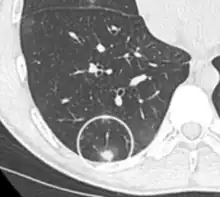

CT image showing patchy areas of ground-glass opacities representing pulmonary edema.